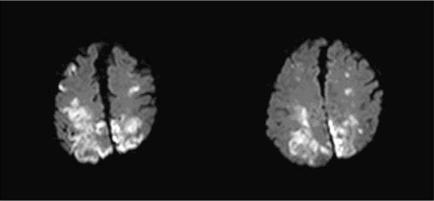

Heart failure (HF) is a complex clinical syndrome that can result from any structural or functional cardiac disorder that impairs the ability of the ventricle to fill with or eject blood. Due to the aging of the population it has become a growing public health problem in recent decades. Diagnosis of HF is clinical and there is no diagnostic test, although some basic complementary testing should be performed in all patients. Depending on the ejection fraction (EF), the syndrome is classified as HF with low EF or HF with normal EF (HFNEF). Although prognosis in HF is poor, HFNEF seems to be more benign. HF and ischemic stroke (IS) share vascular risk factors such as age, hypertension, diabetes mellitus, coronary artery disease and atrial fibrillation. Persons with HF have higher incidence of IS, varying from 1.7% to 10.4% per year across various cohort studies. The stroke rate increases with length of follow-up. Reduced EF, independent of severity, is associated with higher risk of stroke. Left ventricular mass and geometry are also related with stroke incidence, with concentric hypertrophy carrying the greatest risk. In HF with low EF, the stroke mechanism may be embolism, cerebral hypoperfusion or both, whereas in HFNEF the mechanism is more typically associated with chronic endothelial damage of the small vessels. Stroke in patients with HF is more severe and is associated with a higher rate of recurrence, dependency, and short term and long term mortality. Cardiac morbidity and mortality is also high in these patients. Acute stroke treatment in HF includes all the current therapeutic options to more carefully control blood pressure. For secondary prevention, optimal control of all vascular risk factors is essential. Antithrombotic therapy is mandatory, although the choice of a platelet inhibitor or anticoagulant drug depends on the cardiac disease. Trials are ongoing to evaluate anticoagulant therapy for prevention of embolism in patients with low EF who are at sinus rhythm.

心力衰竭(HF)是一种复杂的临床综合征,可由任何损害心室充盈或射血能力的结构性或功能性心脏疾病引起。由于人口老龄化,近几十年来它已成为一个日益严重的公共卫生问题。HF的诊断基于临床,没有诊断性检测方法,尽管所有患者都应进行一些基本的辅助检测。根据射血分数(EF),该综合征可分为射血分数降低的HF或射血分数正常的HF(HFNEF)。尽管HF的预后较差,但HFNEF似乎相对良性。HF和缺血性卒中(IS)有共同的血管危险因素,如年龄、高血压、糖尿病、冠状动脉疾病和心房颤动。HF患者的IS发病率较高,在不同队列研究中每年从1.7%到10.4%不等。卒中发生率随随访时间延长而增加。EF降低,无论严重程度如何,都与较高的卒中风险相关。左心室质量和几何形状也与卒中发生率有关,其中同心性肥厚风险最大。在射血分数降低的HF中,卒中机制可能是栓塞、脑灌注不足或两者兼有,而在HFNEF中,机制更典型地与小血管的慢性内皮损伤有关。HF患者的卒中更严重,且与更高的复发率、依赖率以及短期和长期死亡率相关。这些患者的心脏发病率和死亡率也很高。HF患者急性卒中的治疗包括所有当前的治疗选择,以更谨慎地控制血压。对于二级预防,最佳控制所有血管危险因素至关重要。抗血栓治疗是必需的,尽管血小板抑制剂或抗凝药物的选择取决于心脏疾病。目前正在进行试验,以评估抗凝治疗对窦性心律且射血分数降低患者预防栓塞的效果。